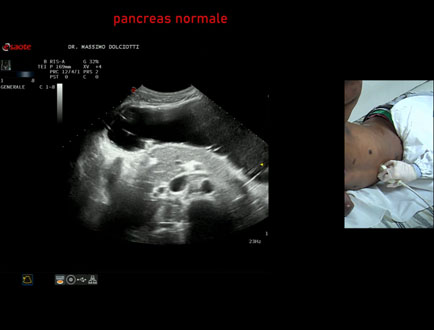

Data inserimento: 21/01/2026

Ecografia del: 14/01/2026

Strumento: Esaote MyLab Eight

Sonda: Convex Multifrequenza 1-8 MHz

Età Paziente: M 29 anni

Motivazione dell'esame: epatopatia virale

Commento all'esame: le immagini ed il video documentano il pancreas ipoecogena, di ecostruttura e morfovolumetria regolare, esaminato in posizione supino e laterale destra.

Conclusioni: pancreas normale (normal pancreas).

In collaborazione: Dr.ssa Marica Manfredi - Ancona, Dr. Ilir Qose - Ancona

Presentazione: Dr. Massimo Dolciotti - Ancona